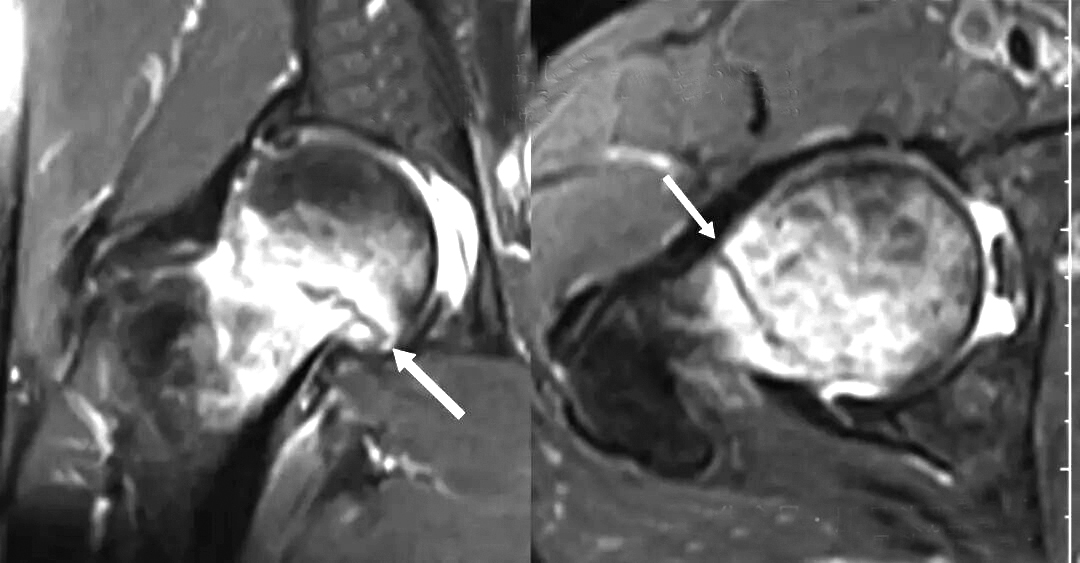

在日常生活中,人们通常认为骨折是摔倒、碰撞等明显外伤导致的结果。但在临床上,不少人在没有明显外伤的情况下发生了骨折。61岁的张先生就遇到了这样的蹊跷事:既往体检结果正常的他,无明显原因出现右侧腹股沟疼痛。他来到医院就诊,做了相关检查。 我们来看下MRI(磁共振成像)横断面成像:股骨头坏死还是骨髓水肿综合征?都不是!看箭头所示,一条明显的“黑线”——这是骨折线。 对于张先生这种没有明显外伤就出现的骨折,可以理解是长期应力造成的。 从发病人群看,应力性骨折有着鲜明的特征。绝经后骨质疏松的老年女性、长期进行高强度训练的运动员及农村长期从事体力劳动的人都是其高发人群。 发病早期,CT片或X线片通常无法显示骨折线,主要是因为其影像学原理依赖骨结构的密度变化,而应力性骨折初期的损伤多发生在骨髓和微细骨小梁,尚未形成明显的骨皮质断裂或骨密度改变。此时,MRI的敏感性优势得以体现:虽然X线或CT检查难以发现结构性断裂,但是MRI能通过信号变化捕捉到骨骼的“求救信号”。 简而言之,MRI在应力性骨折早期虽然未必“看到”骨折线,但是能“感知”到骨骼的病理变化,为临床提供超前诊断依据,避免延误治疗时机。 需要强调的是,应力性骨折常与骨骼疲劳、骨重塑失衡或骨强度下降等相关,这些基础问题可能影响骨折的愈合速度。 对于应力性骨折,如何治疗? 一旦确诊为应力性骨折,治疗方案的选择需要根据骨折的具体情况而定。对于骨折端稳定、移位风险较小的患者,可考虑保守治疗(适当制动、充分休息、抗骨质疏松治疗等)。保守治疗对患者的依从性要求较高,且失败率相对较高,必须在专业医生的指导下进行。如果影像学检查显示骨折端存在明显骨小梁断裂、吸收,骨折端不稳定,或者患者难以配合保守治疗,为避免病情恶化,引发股骨头塌陷等严重后果,需要考虑手术治疗(内固定术、关节置换术等)。 (作者供职于河南省洛阳正骨医院) |